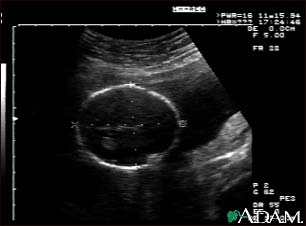

Ultrasound, normal fetus - head measurements

This is a normal fetal ultrasound performed at 19 weeks gestation. Many health care providers like to have fetal measurements to verify the size of the fetus and to look for any abnormalities. This ultrasound is of a head measurement, indicated by the cross hairs and dotted lines.